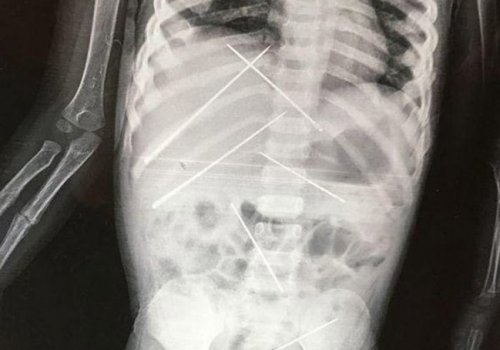

3 yaşlı qızın rentgen kağızı həkimləri dəhşətə gətirdi - FOTOLAR 07.10.2017, 18:52 / DÜNYA DAHA ƏTRAFLI